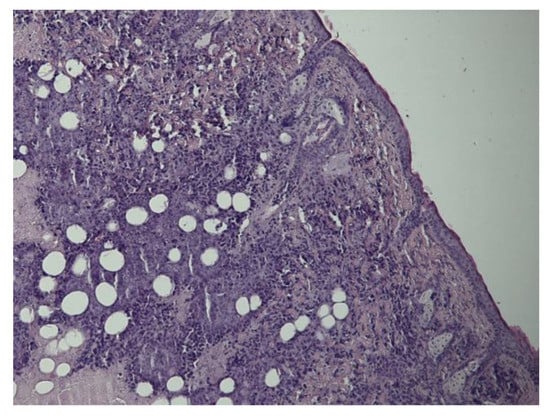

3.2.4. Group IV: EcPHL- and mNP-Treated Mice

- EcPHL improves mNP distributions and the spread radius in the tumor tissue from the local inoculation point in comparison to mice tumor tissue without immunomodulation. The mNP were observed in the necrotic areas and fatty and connective tissues, as well as in the TAMs, both intra- and extracellularly. Intracellular iron-containing exogenous pigments were visible in the cytoplasmic granule. A large number of mNP were observed in inflammatory infiltrates, necrotic areas, and macrophages.